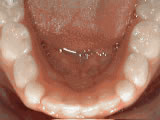

Spacing of teeth

Patient was bothered by the spaces between his teeth. Braces closed the spaces and gave him an ideal bite in 24 months. Special glued-in retainers help keep the spaces closed.